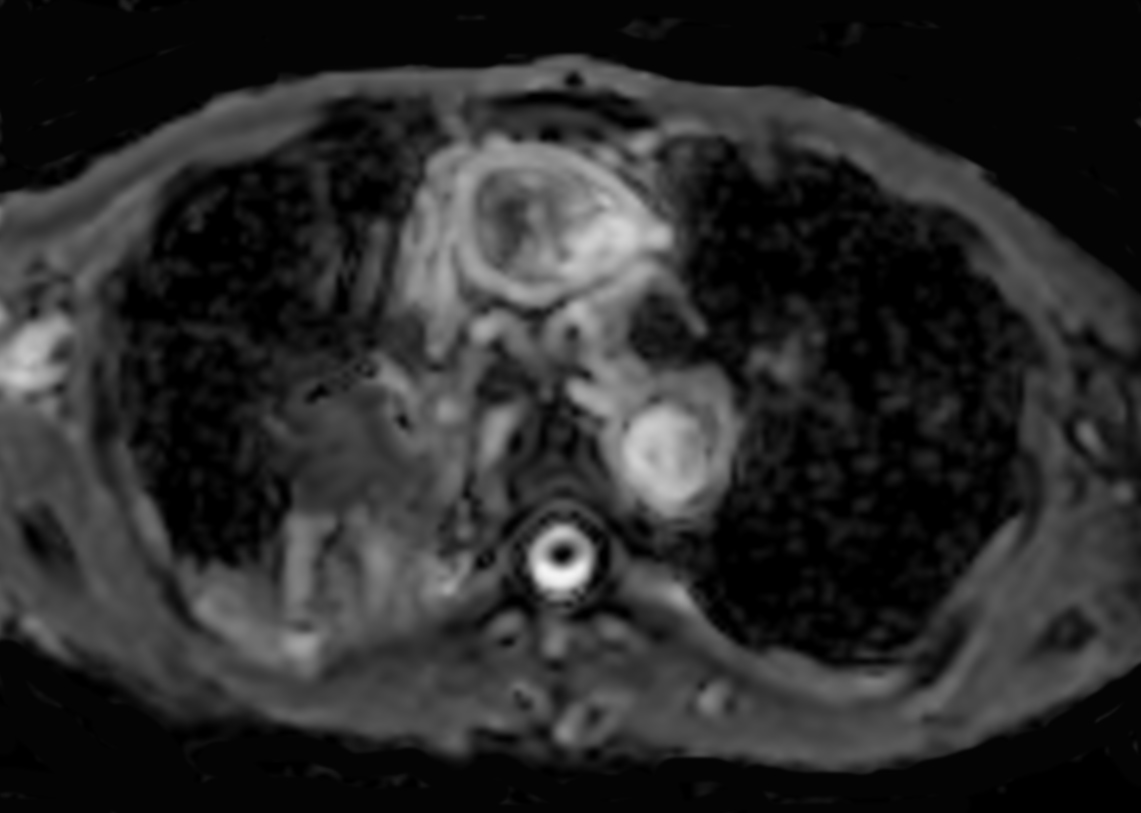

Patient with lung cancer. The ExamCard includes techniques for efficient fat-free imaging over large field-of-views (mDIXON XD), a diffusion procedure with less distortion (DWI TSE XD), a multi-phase contrast-enhanced sequence (4D FreeBreathing) to improve imaging confidence and Compressed SENSE to accelerate the entire exam.

DWI TSE XD b1000 Compressed SENSE